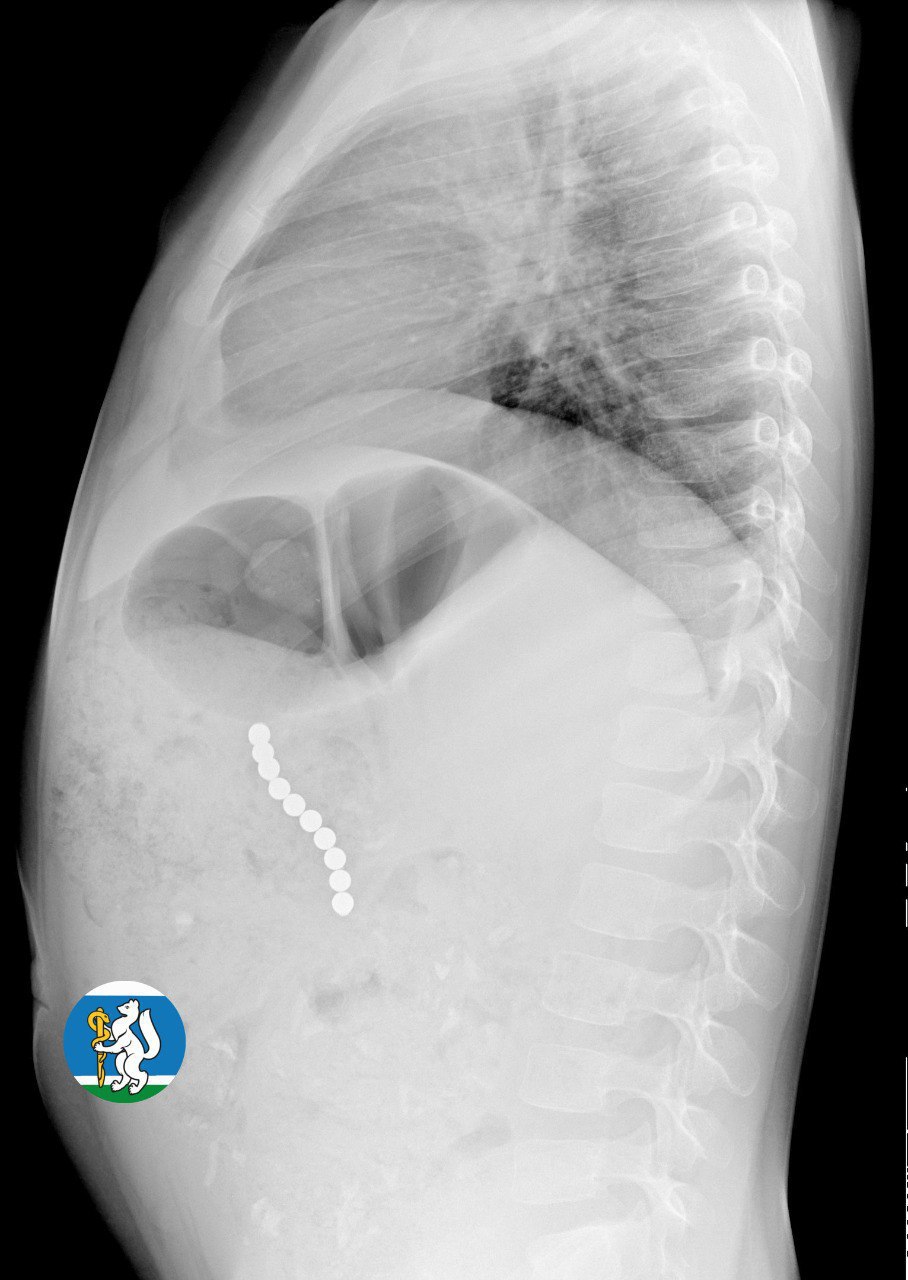

Как сообщили в пресс-службе областного минздрава, шарики соединились друг с другом через стенки внутренних органов и повредили их. Цепочка из опасных предметов длиной 5 сантиметров могла привести к перитониту и гибели ребенка. К счастью, родители вовремя обратились к участковому педиатру, который направил девочку на рентген. Увидев на снимке цепочку из магнитных шариков, медики направили Ульяну в детскую городскую клиническую больницу № 9, где ее прооперировали.

«Для минимизации риска осложнений удаление инородных тел было проведено интраоперационно. В ходе вмешательства дежурная бригада врачей извлекла 10 магнитных шариков, цепочка которых в длину составила 5 сантиметров», – рассказал детский хирург ДГКБ № 9 Андрей Чукреев.